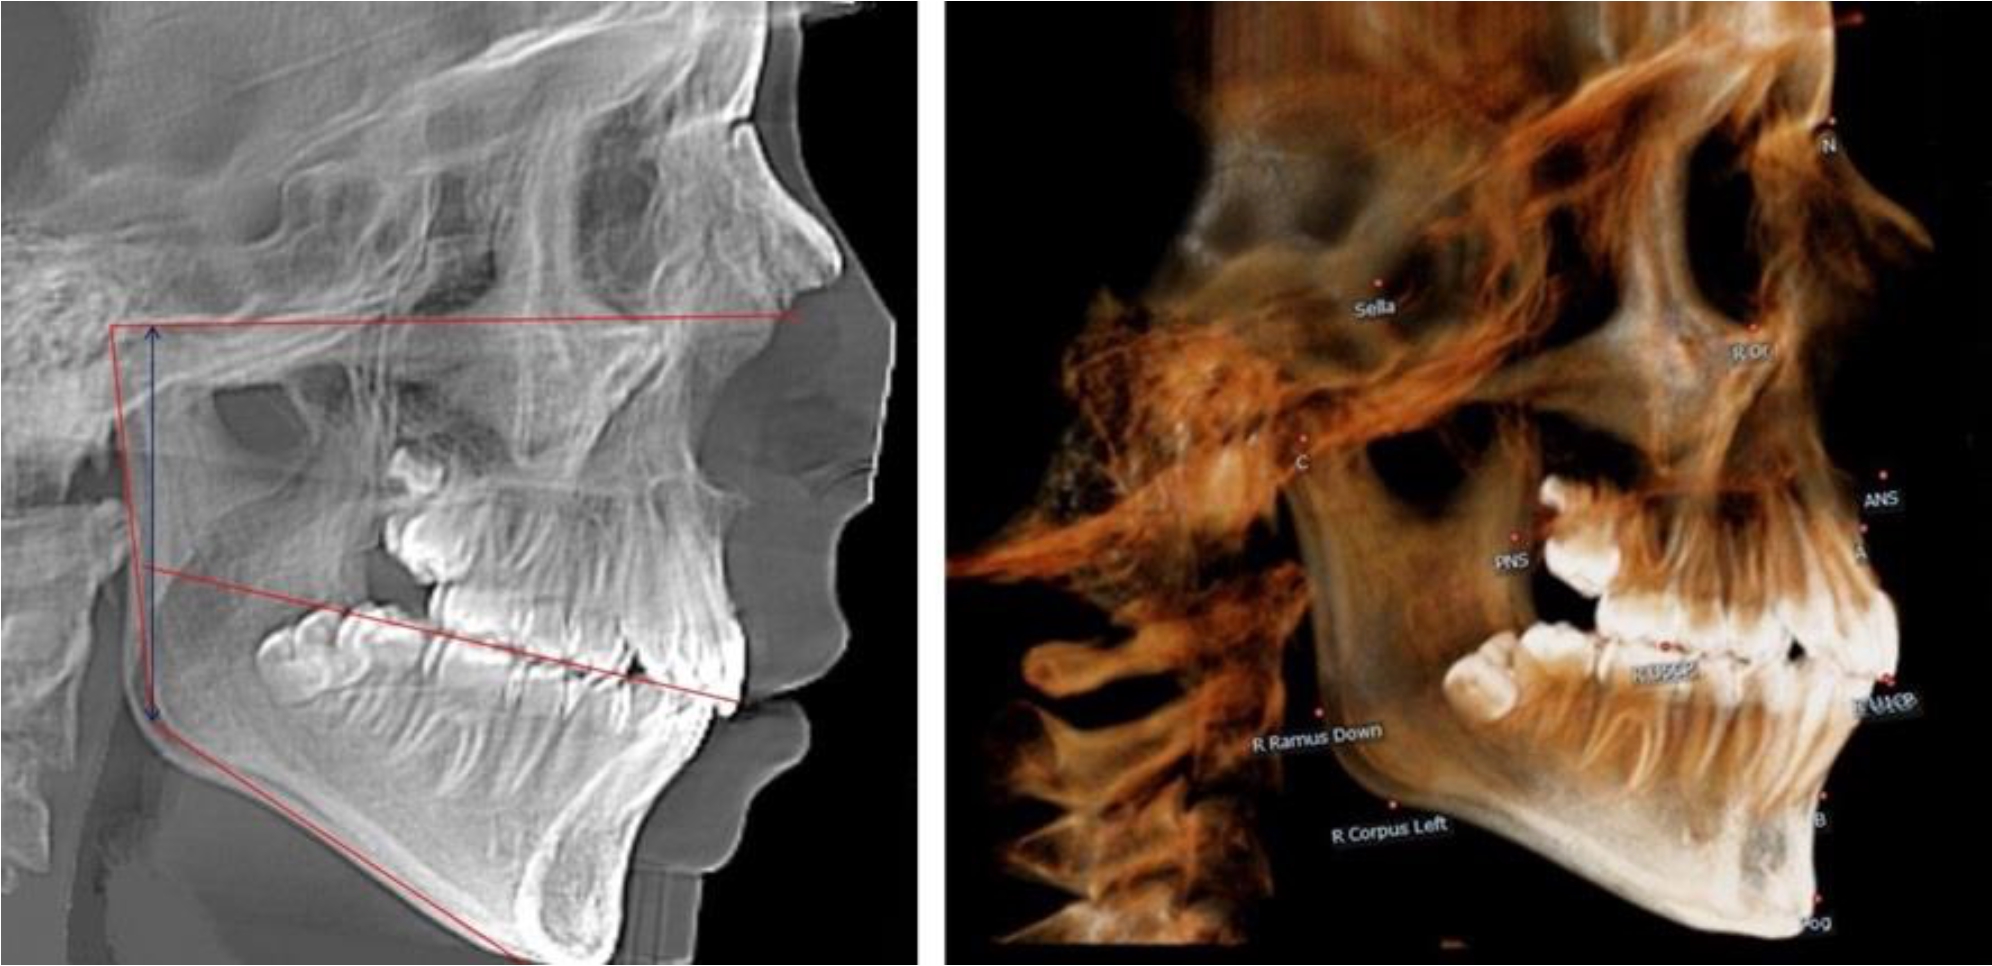

В 5-й группе были проанализированы 14 комплектов рентгенограмм, что составило (13,21 ± 3,29) % от общего числа. На всех рентгенограммах отмечен очередной этап подъема высоты прикуса, обусловленный прорезыванием вторых постоянных моляров. Окклюзионная линия делила ветвь на два отдела (рис. 5).

Рис. 5. ТРГ и ОПТГ пациента после смены молочных зубов и прорезывания вторых постоянных моляров

Высота ветви у детей 5-й группы составляла (62,87 ± 3,62) мм, что было достоверно больше, чем у детей других групп (р ˂ 0,05). При этом высота верхней окклюзионно-суставной части была (40,23 ± 2,01) мм, а нижней – (22,64 ± 1,78) мм. Высота верхней части была вдвое больше нижней, что и определяло особенности соразмерности частей ветви нижней челюсти в анализируемый возрастной период.

Относительные показатели соразмерности частей ветви нижней челюсти показали, что отношение высоты верхней части ветви к нижней в среднем составляло 1,78 ± 0,18. Отношение общей высоты ветви к верхней ее части составляло 1,56 ± 0,12, а отношение общей высоты ветви к нижней ее части было 2,78 ± 0,14, что и определяло особенности соразмерности частей ветви нижней челюсти в анализируемый возрастной период.